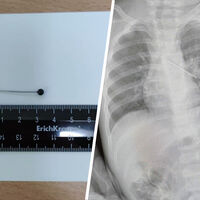

Врачи Центра охраны материнства и детства спасли 17-месячного ребенка, который из любопытства проглотил булавку. Об этом сообщила президент медицинского учреждения Лариса Белоцерковцева в Telegram-канале.

По словам медика, мать мальчика вовремя заметила беду и привезла ребенка в медицинское учреждение. Обследование показало, что инородный предмет зафиксировался в бронхах.

«Если бы бригада наших высокопрофессиональных специалистов не смогла удалить инородный предмет с помощью бронхоскопа, ребенка пришлось бы передавать торакальным хирургам для проведения большой операции», — пояснила Белоцерковцева.